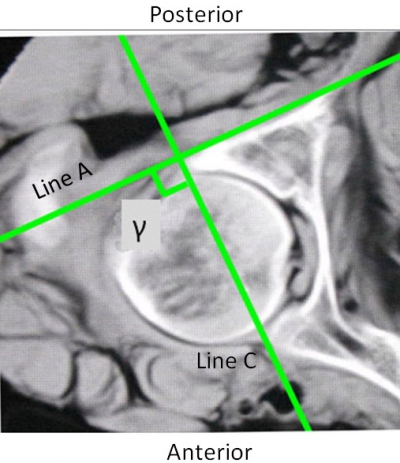

Sixteen embalmed adult cadavers were obtained from the Department ofAnatomy of Hebei Medical University (Shijiazhuang, China). The specimens wereall males with an average age of 41 years (range, 25-70 years). The specimenswere placed in the supine position on a radiolucent carbon fibre table. Thelongitudinal axis of the specimen was parallel to that of the table. CT scanswere performed on all specimens using a commercially available Siemens spiral64-slice multi-detector scanner (Siemens Medical, Nuremberg, Freistaat Bayern,Germany). The technical factors were 80-110 mAs, 120 kV, pitch 0.9 and anacquisition thickness of 0.75 mm. Axial images with a 2-mm thickness werecreated. The CT images of each specimen were observed and no bony deformity wasnoted. Previous anatomical study has shown that the smallest axialcross-section of the posterior column is at the middle height level of theacetabulum . The axial CT image at the level of the middle height of theacetabulum was selected. The PCPC was identified on the selected CT image and labelledLine A (Figure 1). The line intersecting the axial plane and the coronal planewas marked, which could be identified by drawing a line running through themost posterior points of bilateral acetabula. The angels between Line A and theline intersecting the axial plane and the coronal plane were measured using themeasurement software MB ruler (Markus Bader, Iffezheim, Germany) and labelledangle α. The medial wall of the acetabulum was also outlined and labelled LineB. The angle between Line B and the line intersecting the axial plane and the sagittalplane was labelled angle β and measured using an MB ruler (Figure 1). The line that ran through the anterior and posteriorpoints of the lateral brim of the acetabulum on the selected axial CT images waslabelled Line C. The angle between Lines A and C was marked and measured, and waslabelled angle γ (Figure 2).

Figure2 On the axial CT images, Line C represents the line runningthrough the anterior and posterior points of the lateral brim of theacetabulum. The angle between Lines A and C is labelled angle γ.